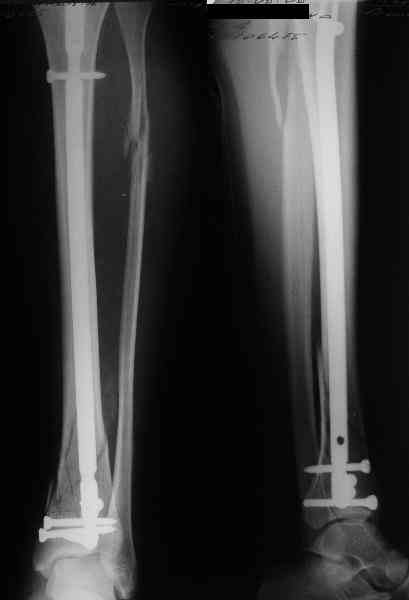

В приложении пример лечения аналогичного повреждения (плюс задний край).

Выполнил MIPO предизогнутой метафизарной LCP

Красиво получилось, поздравляю. Насчет немедленной полной нагрузки, как на гвозде, про что Алексей Семенистый говорит - будете разрешать сразу?

И все же немного критики:1) Вы добивались анатомичной репозиции, которая требует абсолютной стабильности, которая в свою очередь возможноа только в условиях межфрагментарной компрессии. Пластина уложена как мостовидная, не хватает стягивающнго винта. 2) есть укорочение малоберцовой кости, необхордимо восстановить ее длину! В таком виде я бы не стал разрешать раннюю нагрузку. Добавить самую малость: стягивающий винт и остеосинтез малоберцовой кости и больной может наступать сразу.